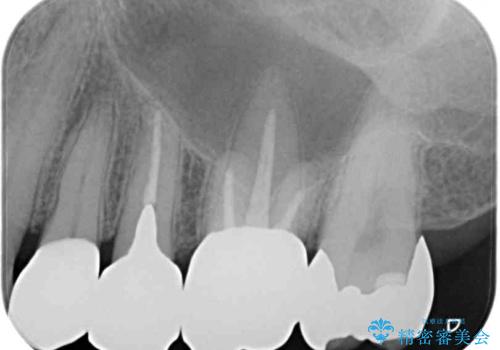

精査の結果、詰め物の下に虫歯が大きく広がっているのがわかりました。

外見からはあまり大きな虫歯があるようには見えなくても、X線検査をすることで、詰め物の下に虫歯が広がっていることは多々あります。